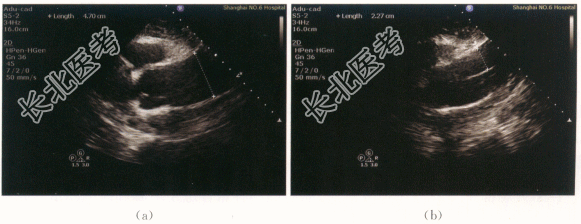

- [材料题] 患者,男性,62岁,因“胸前区疼痛6小时”就诊。患者下午5时左右,无明显诱因出现胸前区针刺样疼痛,向背部放射,伴大汗淋漓,伴头晕,无胸闷,无头痛,无恶心呕吐,无气急,无心悸等不适,未就诊,休息后症状无缓解,胸痛症状较前明显,向中下腹部腰部放射,伴胸闷、头晕,无恶心呕吐,无气急等,下午7时到我院急诊。体格检查:患者血压110mmHg/67mmHg,神志清醒,气平,无贫血貌,双肺听诊呼吸音清,肺底未及啰音。心浊音界大致正常,心率52次/min,律齐,P2=A2,主动脉瓣听诊区可及3/6级舒张期吹风样杂音。腹壁柔软,无腹部压痛。双下肢无水肿。实验室检查及特殊检查:血WBC升高,RBC及Hb下降,N增高,ESR增快,D-二聚体升高。心肌酶谱升高,蛋白尿。心电图:窦性心律,Ⅰ度房室传导阻滞,LⅢ呈QR型。影像资料: